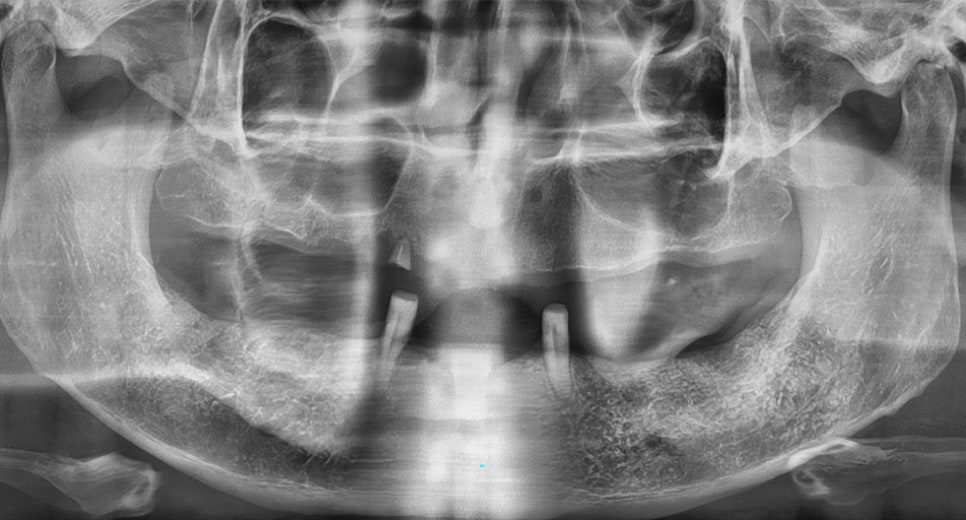

치아를 모두 상실한 분들을 위한 전체 임플란트

전체 임플란트란 심한 충치나

잇몸 질병, 사고 등의 이유로 개인의

모든 치아를 상실한 경우에 본래의

치아처럼 회복하기 위해 임플란트로

전체 치아를 복구하는 방법입니다.

전체 임플란트는 치료 범위가 크고

난이도가 높은 수술이기에 숙련된

의료진의 충분한 임상경험과 교합에

대한 명확한 이해 및 섬세한

기술력이 중요합니다.